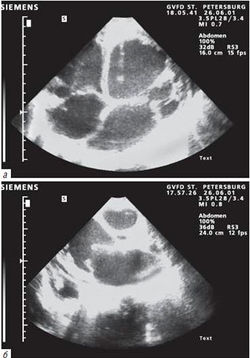

ЭхоКГ при ПМК. K. Joseph и соавт. (1987) рекомендуют определять степень пролабирования створок следующим образом.

В норме - тела створок располагаются в полости ЛЖ, ниже кольца митрального клапана. При ПМК-I - тела створок (или одной из створок) незначительно прогибаются во время систолы ЛЖ в полость левого предсердия; концы створок находятся в полости ЛЖ, ниже линии кольца митрального клапана.

При ПМК-II - тела створок МК (или створки) более значительно прогибаются в левое предсердие, концы створок - на линии кольца МК.

При ПМК-III - тела створок (створки) находятся в полости левого предсердия, выше линии кольца МК.

Согласно рекомендациям Н.М. Мухарлямова (1981) степень ПМК по данным ЭхоКГ соответствует следующим показателям:

- I степень - пролабирование до 6 мм;

- II степень - пролабирование 6-9 мм;

- III степень - пролабирование свыше 9 мм.